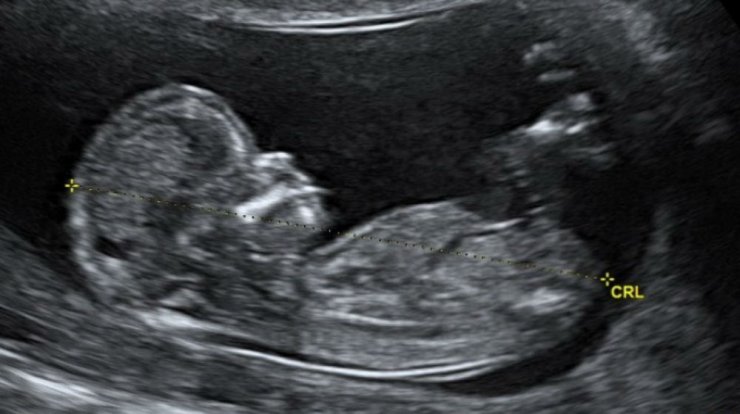

Πριν από μερικές ώρες ο τραγουδιστής ανήρτησε στον προσωπικό του λογαριασμό στο instagram, το υπερηχογράφημα του μωρού τους, ενώ κατόπιν, μοιράστηκε και κάποιες φωτογραφίες της αγαπημένης του από τον γυναικολόγο, δείχνοντάς μας τη φουσκωμένη της κοιλίτσα, ξεκαθαρίζοντας πως δεν επρόκειτο για πρωταπριλιάτικο ψέμα.